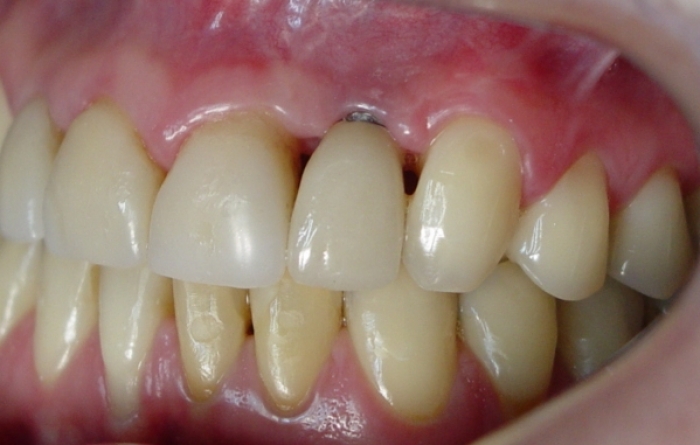

Porção intermediária do implante exposta

Imagem final após enxerto de gengiva, troca da prótese fixa sobre o implante e tratamento reabilitador